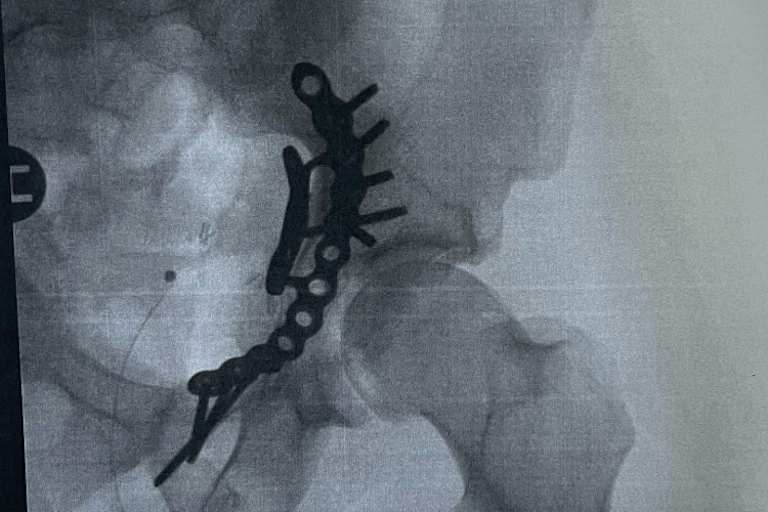

Am vergangenen Donnerstag war Pedersen transportfähig und wurde von Polen nach Dänemark geflogen, zwei Chirurgen in Odense nahmen die Hüft-OP vor. "An der Vorderseite des Beckens wurden eine Platte und Schrauben eingesetzt, um den Bruch zu fixieren", teilte er mit. "Die Nerven sind intakt, aber der Knorpel um die Hüftschale ist beschädigt. Für die nächsten acht Wochen darf ich mein linkes Bein wenig belasten."